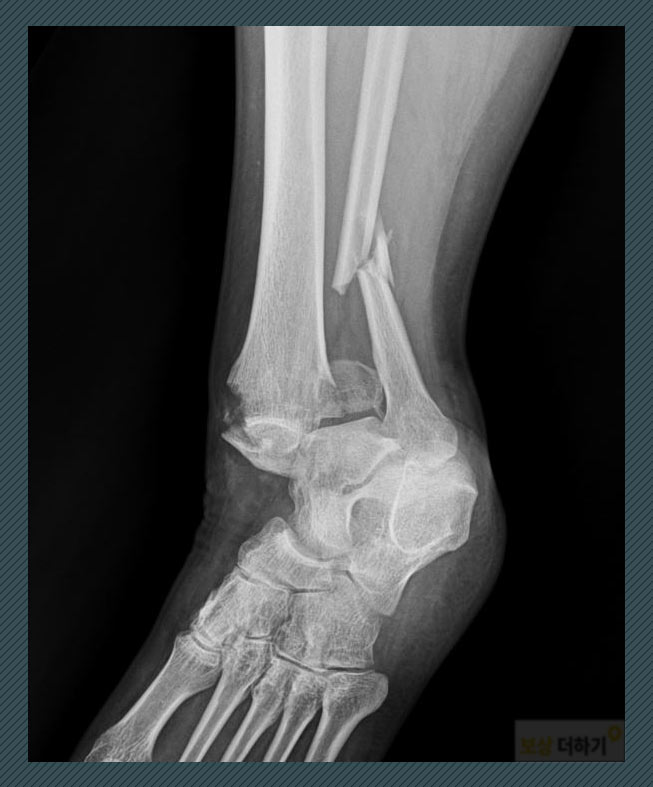

오늘 소개드릴 사례자는 미끄러운 지면 길을 걷다가 넘어지면서 다치셨습니다. 겨울철 빙판길이나 빗길에 특히 많이 일어나는 사고입니다. 엑스레이 상 뼈의 모양을 보면 부상이 꽤 심각했다는 것을 알 수 있죠.

진단: S82320 경비골 하단 골절 위의 사진을 참고해 보시면, 다리뼈는 경골과 비골로 구성되어 있어요. 안쪽의 굵은 뼈가 경골, 그 옆의 가는 뼈가 비골인데요. 두 곳에 모두 부상을 입은 것입니다. 경비골 하단(원위 경비골) 즉 발목 쪽에 골절이 되면서 수술이 필요한 상황이었습니다.